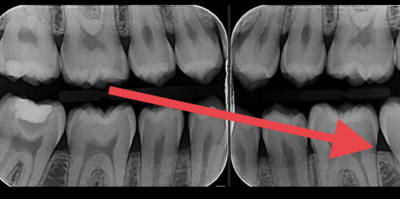

ci joint les radios, pour la 47 il ya une résine avec un fond de cavité

C est quoi ce fond de cavité qui est totalement radio-transparent ???

Clairement... C est a peine moins radio opaque que la dentine. La c est quand même très très radio clair...

Pour moi la c est de la biocarix... ;)

De toute façon y a un truc louche de l’autre coté avec de la biocarix à l’intérieur aussi

Non ça c est la projection de la convexité de la racine distale qui crée une zone radioclaire.

oui pourquoi pas. De toute façon ça ne coûte rien de démonter la restauration de 47 et de voir si il y a bien de la biocarix

un peu trop radio clair à mon gout pour etre honnete....